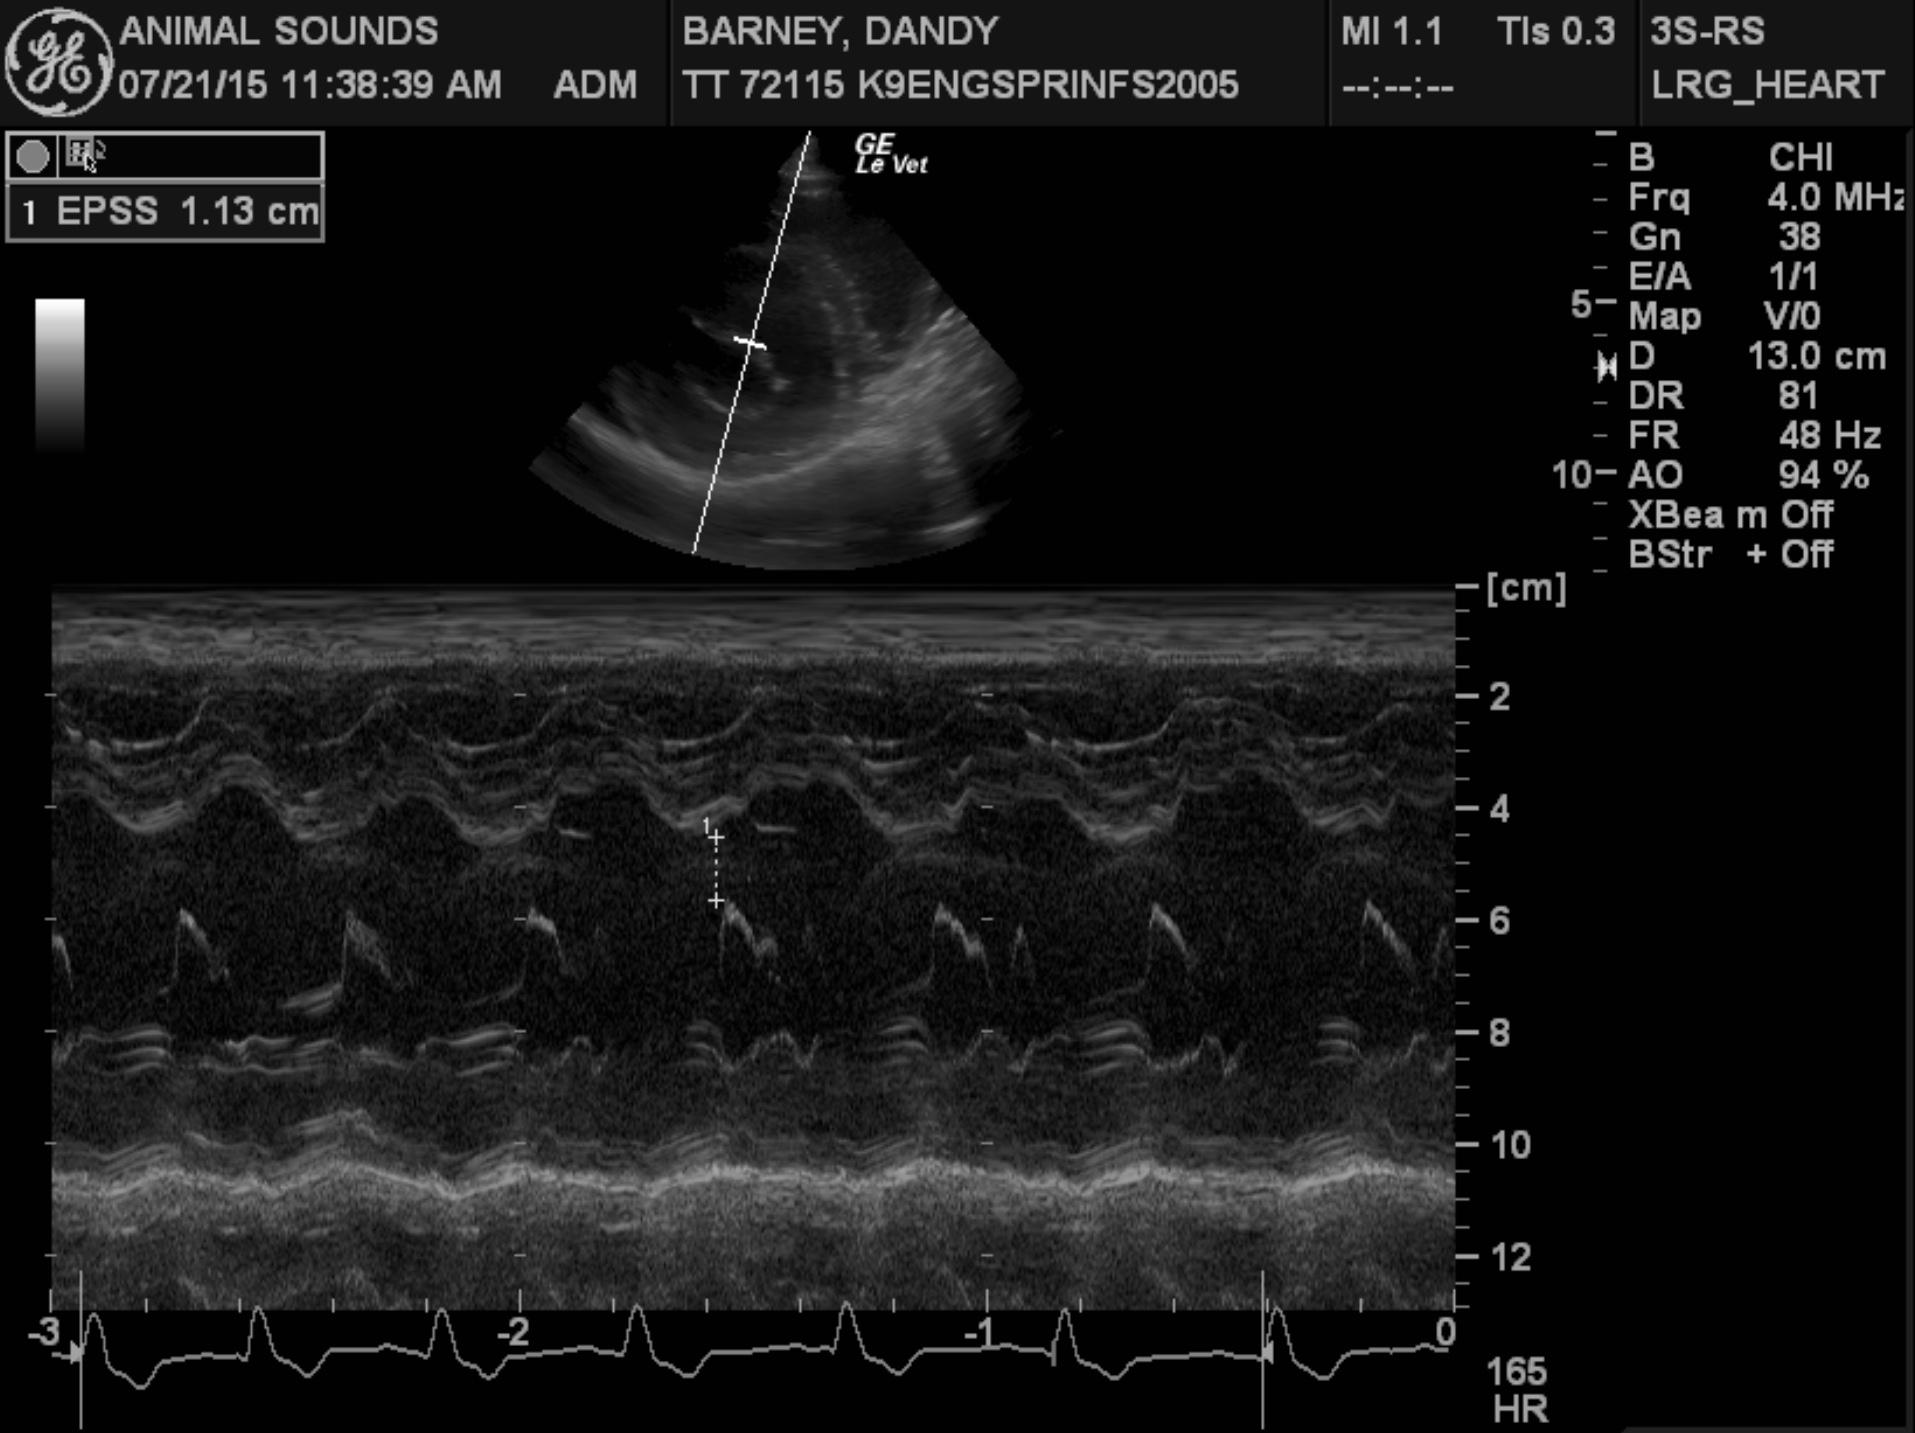

Echocardiogram findings: There is moderate to severe left ventricular dilation. The mitral valve appears normal, though a mild jet of central mitral regurgitation is present. Left ventricular systolic function is globally depressed. The aorta and aortic valve are normal. Right atrial and right ventricular dimensions are normal. The tricuspid valve appears normal, though trace physiologic tricuspid regurgitation is present. The pulmonary artery and pulmonic valve are normal. No pericardial effusion or cardiac masses are seen.

EPSS – 1.13

This examination demonstrates global left ventricular systolic dysfunction, consistent with dilated cardiomyopathy. Secondary to the patient’s myocardial dysfunction, she has severe left ventricular dilation, as well as moderate to severe left atrial dilation, and it appears that she is in mild congestive heart failure based on her thoracic radiographic findings. Given the severity of her cardiac disease, it appears very likely that this is the cause of her arrhythmia.